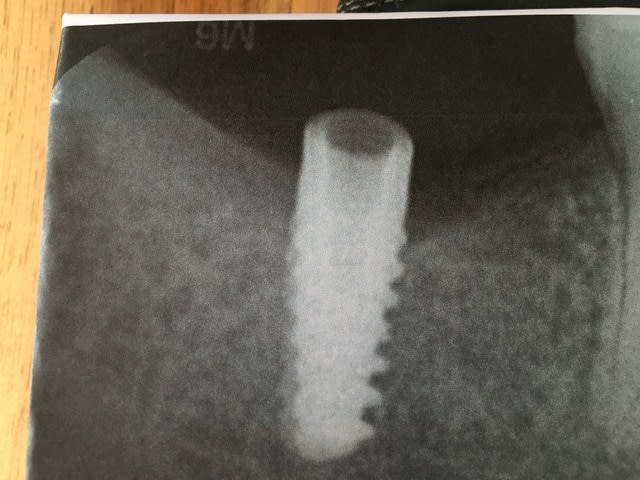

Pouvez vous me dire le nom de cet implant

comme çà a chaud sinon çà pourrait peut être coller avec un Naturactis ETK....mais là niveau fiabilité on est à 20%.....